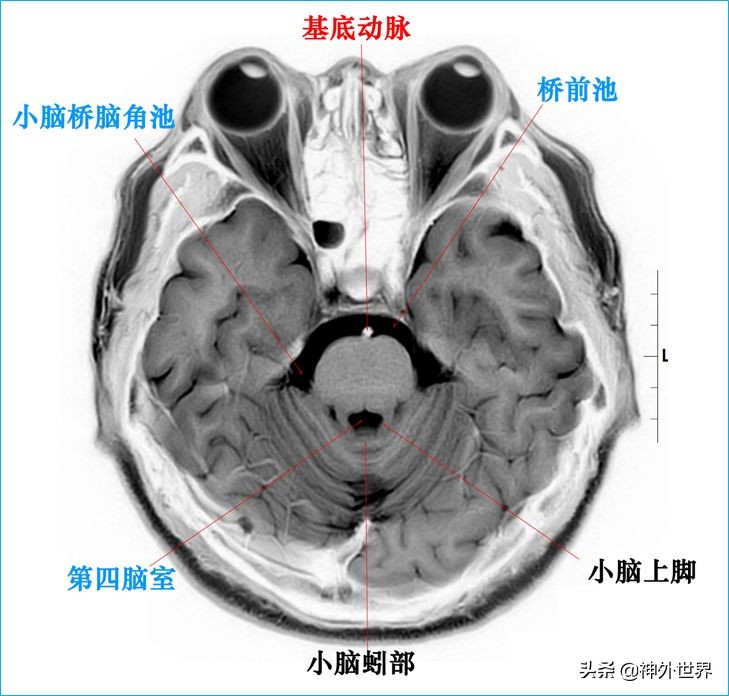

四、T2WI反相图学颅脑断层解剖

以下图片均来自我院3.0T核磁共振的T2WI反相图。标注均为我自己完成,水平有限,难免有误,还望各位老师多多指正。谢谢。